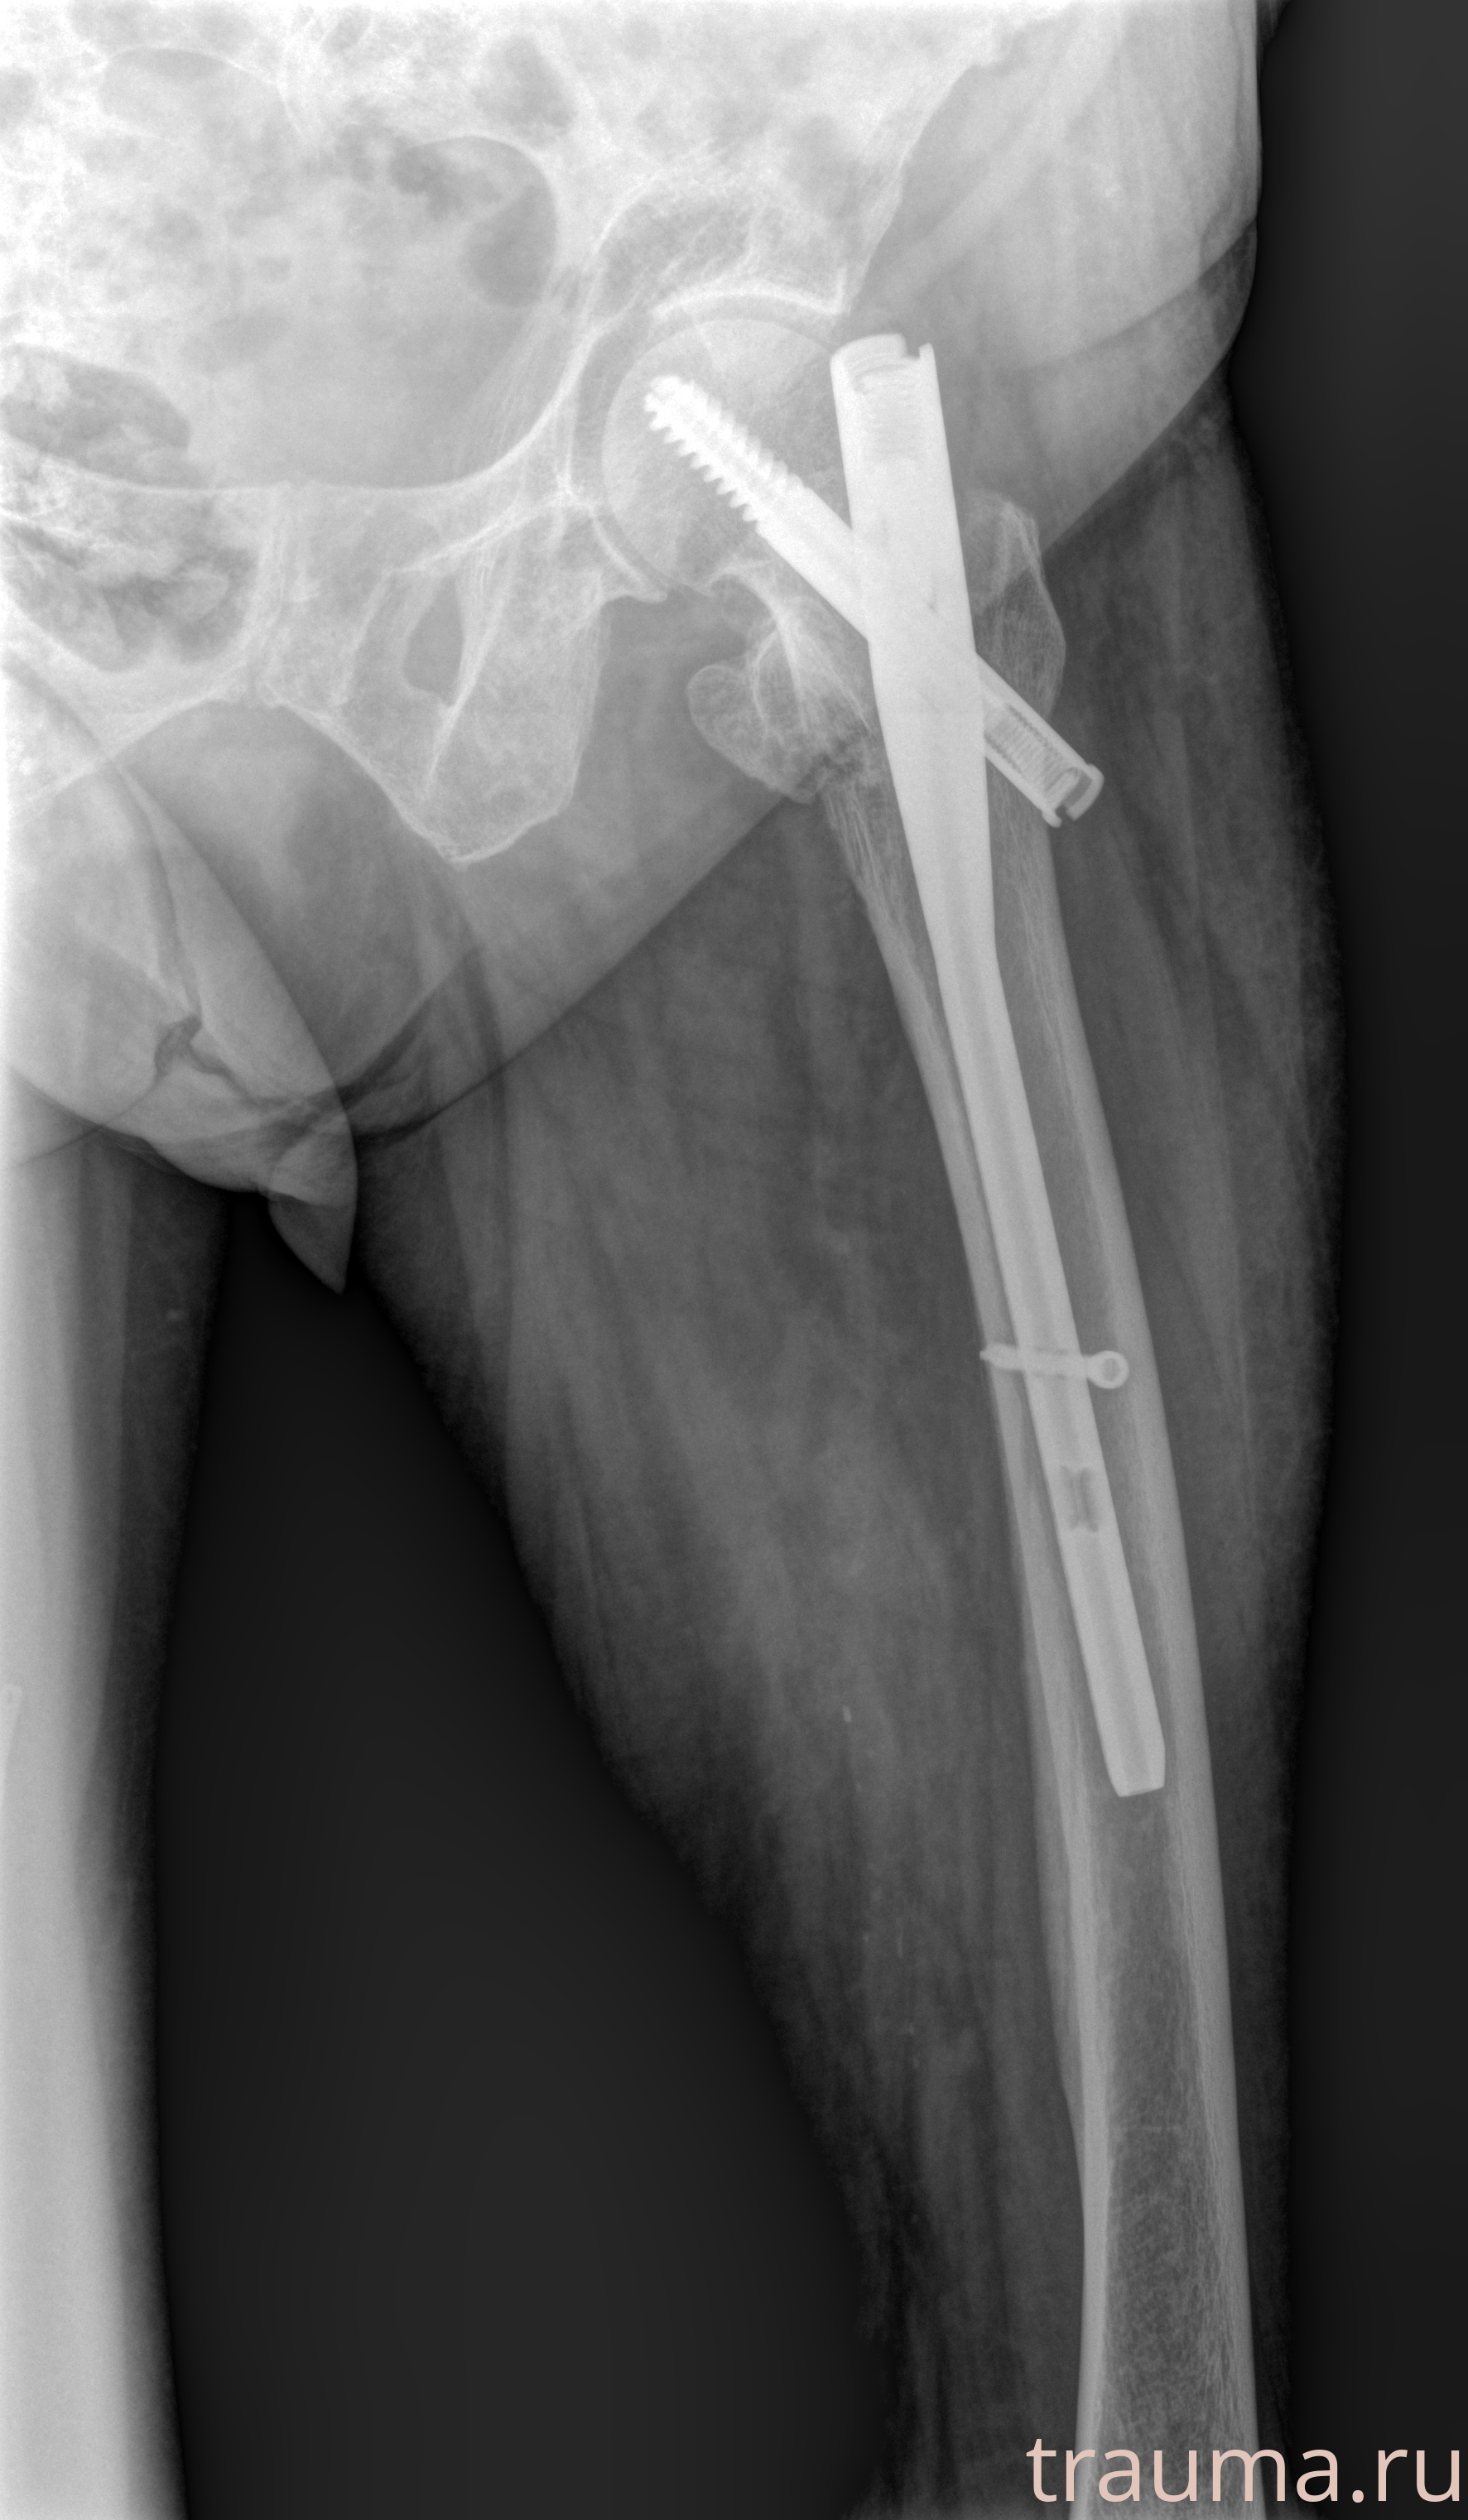

Рентгенограммы

Рентген на дому: по вашему адресу приезжает врач-рентгенолог, травматолог-ортопед с мобильным рентгеновским аппаратом, проводит диагностику травмы или заболевания, делает необходимые рентгенограммы, дает рекомендации по дальнейшему лечению. Получить качественные снимки в домашних условиях возможно благодаря уникальной методике, разработанной МосРентген Центром для института  Склифосовского